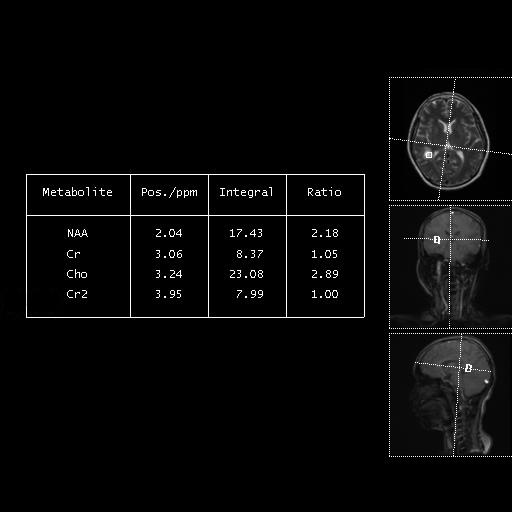

• 肿瘤样脱髓鞘病变报道3例

2023, 48(5):614-617. DOI: 10.13406/j.cnki.cyxb.003183

摘要 (95) HTML (24) PDF 1.29 M (241) 评论 (0) 收藏

摘要: